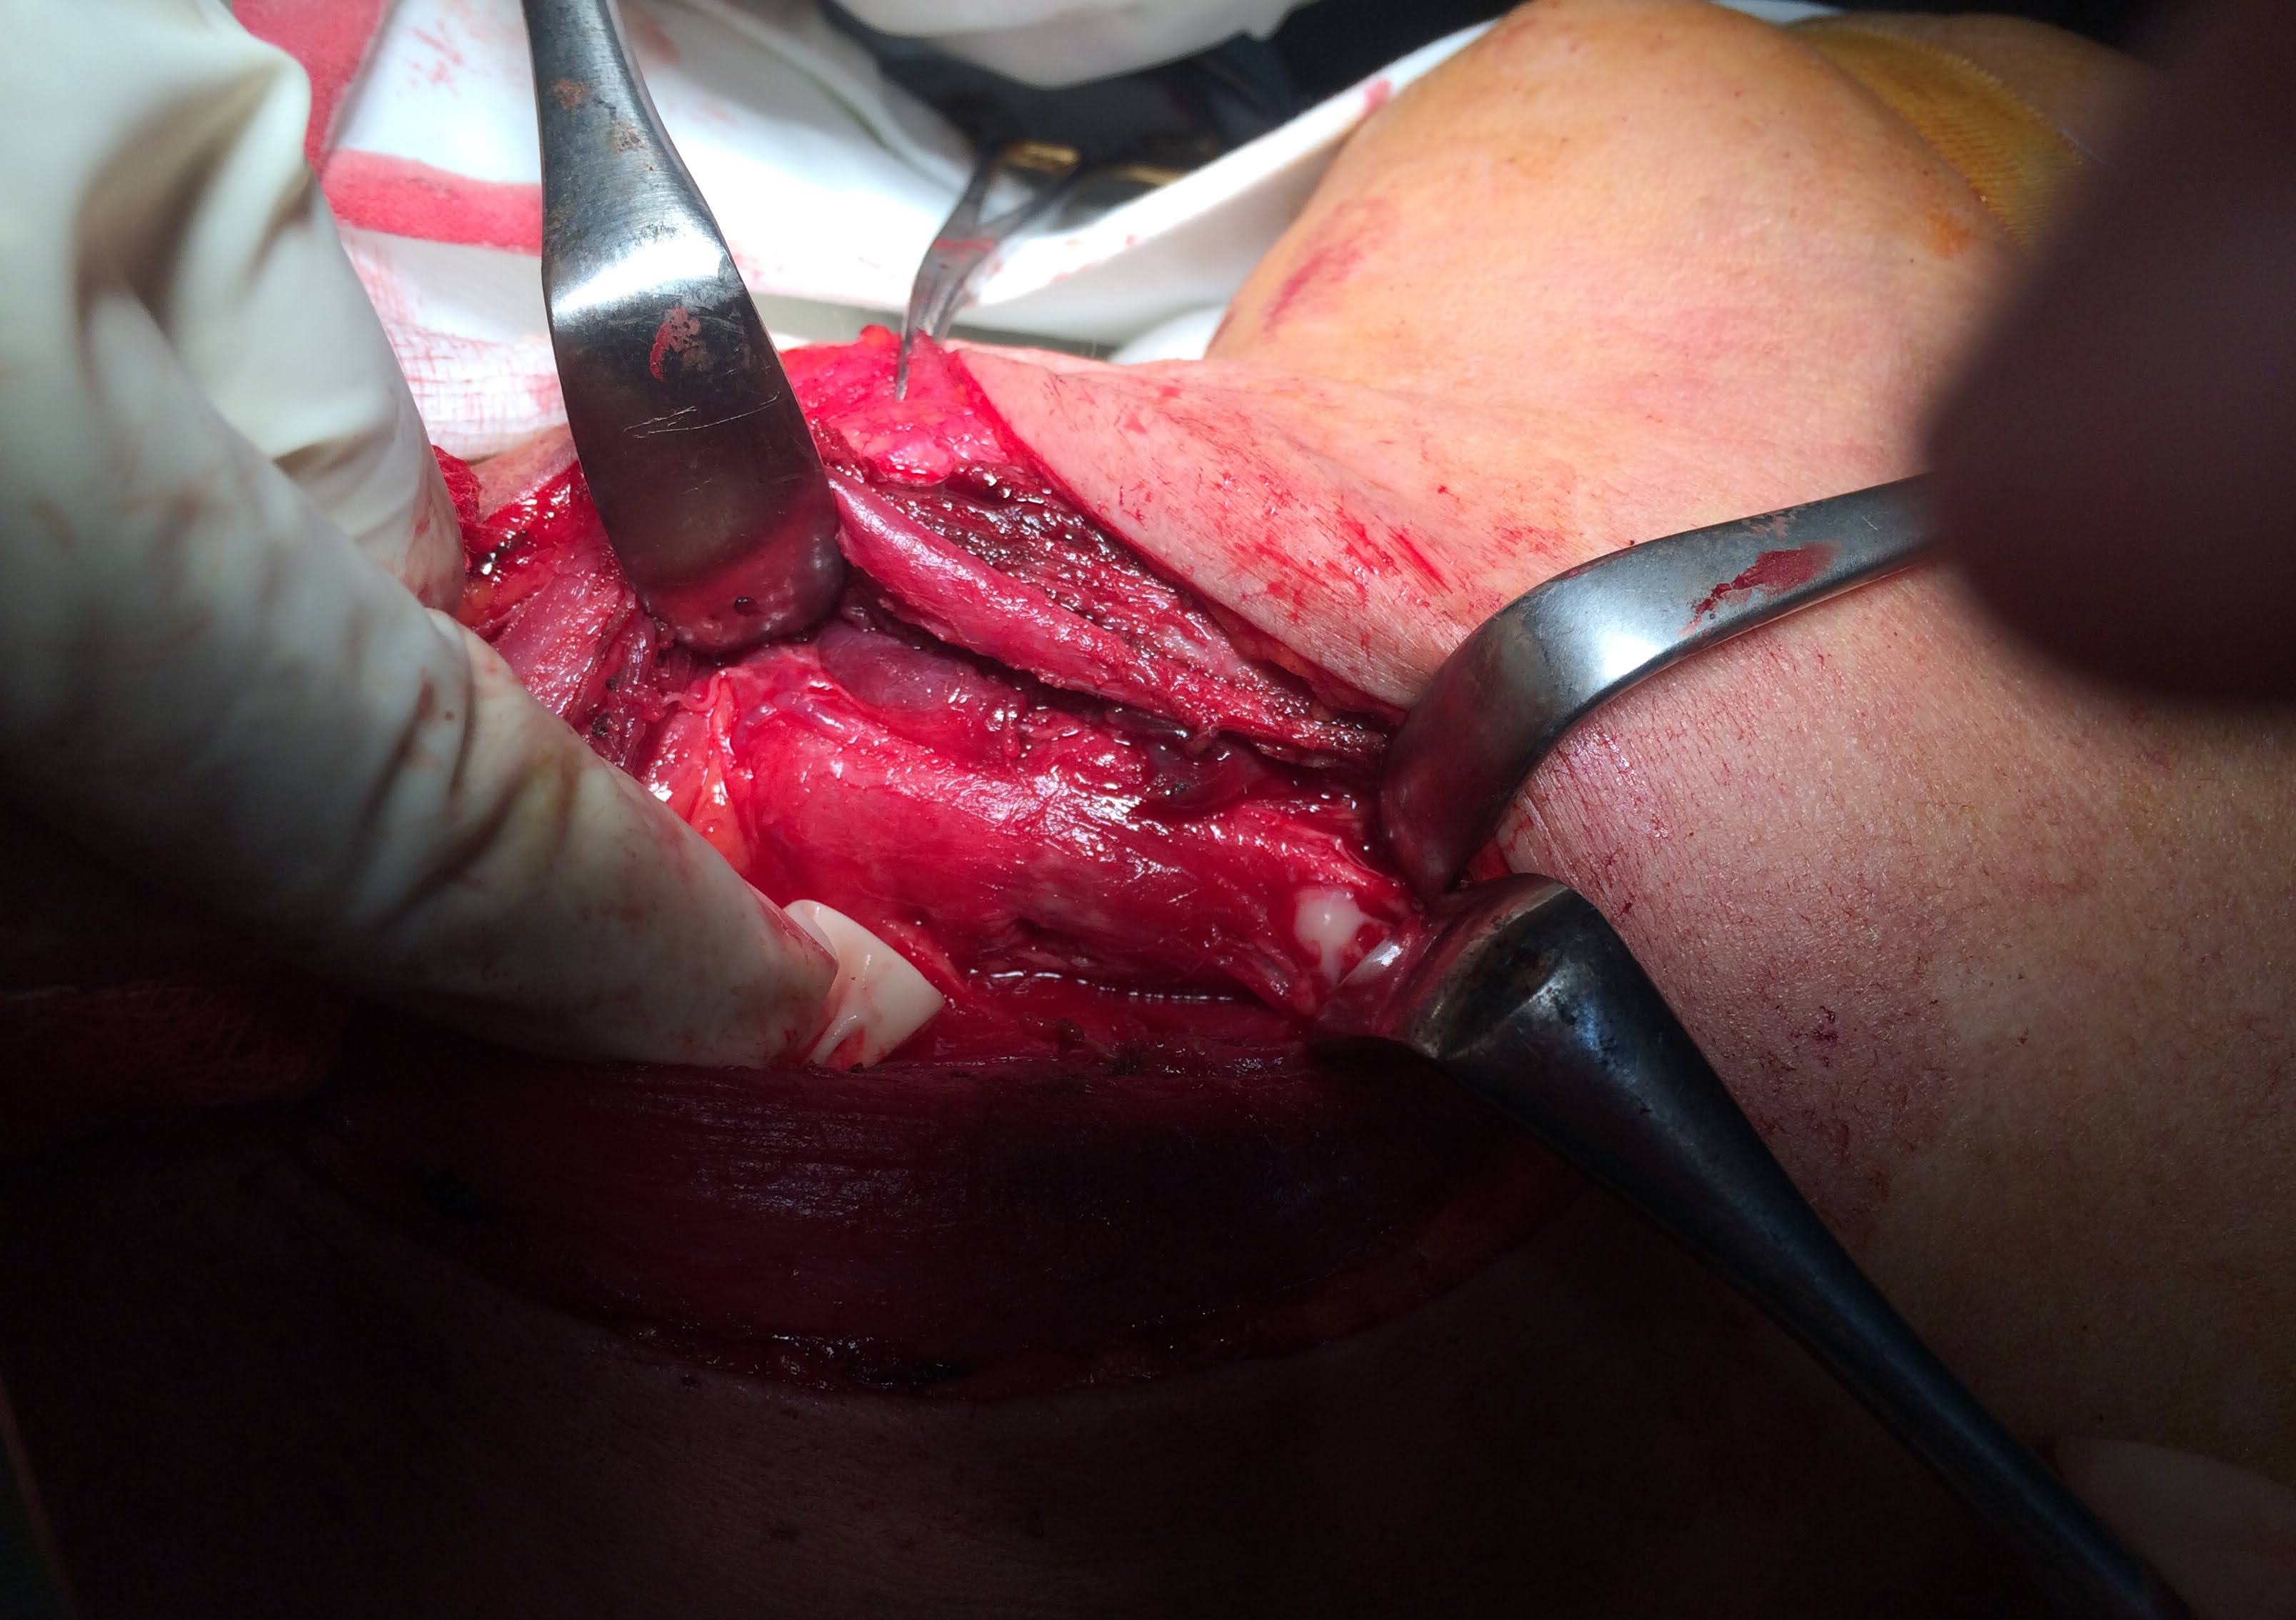

Chúng tôi mô tả một trường hợp bệnh cấp cứu đồng thời áp-xe tuyến giáp kèm nhiễm trùng cổ sâu ở khoang trước sống và khoang nguy hiểm. Bệnh nhân nữ Đ.T.N. Hương, 56t, có bệnh lý đái tháo đường không điều trị thường xuyên. Bệnh nhân không có tiền sử hóc xương, không có tiền sử bệnh lý tuyến giáp trước đó. Bệnh nhân có biểu hiện nuốt đau, kèm sưng nề vùng cổ, sờ thấy khối cứng, sẫm màu, không di động. Siêu âm vùng cổ cho kết quả vùng sau trên thùy giáp trái, trước thực quản có ổ tụ dịch nhiều hồi âm, giới hạn ít rõ, kích thước 23x30x51mm. Hình ảnh chụp cắt lớp vi tính cho thấy ổ áp-xe mô mềm lan rộng thành sau họng, kích thước 27 x 13mm, thâm nhiễm xung quanh. Bệnh nhân được tiến hành mổ cấp cứu dẫn lưu hai ổ áp-xe tránh gây biến chứng chèn ép đường thở và tránh gây nhiễm trùng lan tỏa vào trung thất, nguy hiểm đến tính mạng. Chẩn đoán vi khuẩn gây bệnh dựa vào kết quả lấy dịch mủ nuôi cấy, cho thấy nhiễm khuẩn Klebsiella pneumoniae có ESBL dương tính (men beta lactamase phổ rộng). Điều này có nghĩa vi khuẩn kháng lại rất nhiều các kháng sinh. Đây là gánh nặng thực sự trong điều trị nhiễm trùng trực khuẩn Gram âm, gia tăng chi phí điều trị do phải bắt buộc thay thế các kháng sinh cũ bằng các kháng sinh mới đắt tiền. Hiện tại, tình trạng nhiễm trùng và áp-xe được điều trị ổn định sau khi mở cạnh cổ dẫn lưu và điều trị phối hợp kháng sinh tích cực kèm súc rửa chăm sóc hố mổ hằng ngày.

Chúng tôi xin chân thành cám ơn PGS Thái và các bác sĩ Gây mê đã phối hợp với ekip cấp cứu của Khoa Tai Mũi Họng (Ts Minh A, Bs Nhật và các học viên BSNT) thực hiện nhanh chóng và kịp thời, giải quyết tình trạng nhiễm trùng lan tỏa cho bệnh nhân.